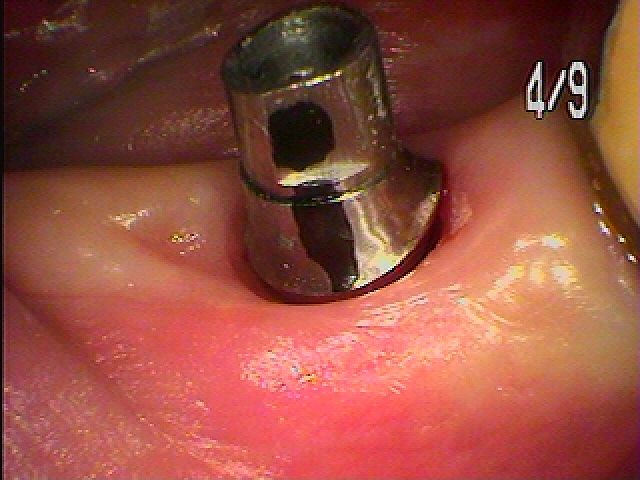

歯肉のクリーピングも起きてきます。| |広島市安佐南区の歯科医院 歯肉のクリーピングも起きてきます。 トップ お知らせ・ブログ 歯肉のクリーピングも起きてきます。 歯肉のクリーピングも起きてきます。 Web診療予約 初めての方へ 選ばれ続ける理由 院内設備について 歯が痛いしみる一般歯科 歯がぐらぐらする歯周病 健康な歯を保ちたい予防歯科 子供の虫歯予防をしたい小児歯科 銀歯をセラミックに審美歯科 白い歯を目指しませんか?ホワイトニング 矯正専門医がいるので安心矯正歯科 抜けた歯を補いたいインプラント・入れ歯 医院案内 スタッフ紹介 メリィハウス歯科クリニックオフィシャルホームページ ラベンダー歯科クリニックオフィシャルホームページ お知らせ・ブログ ホーム 診療科目 一般歯科 歯周病治療 予防治療 小児歯科 審美治療 ホワイトニング 矯正歯科 入れ歯・インプラント マウスピース矯正 初めての方へ 院長・スタッフ 設備紹介 医院案内・アクセス メニューを閉じる